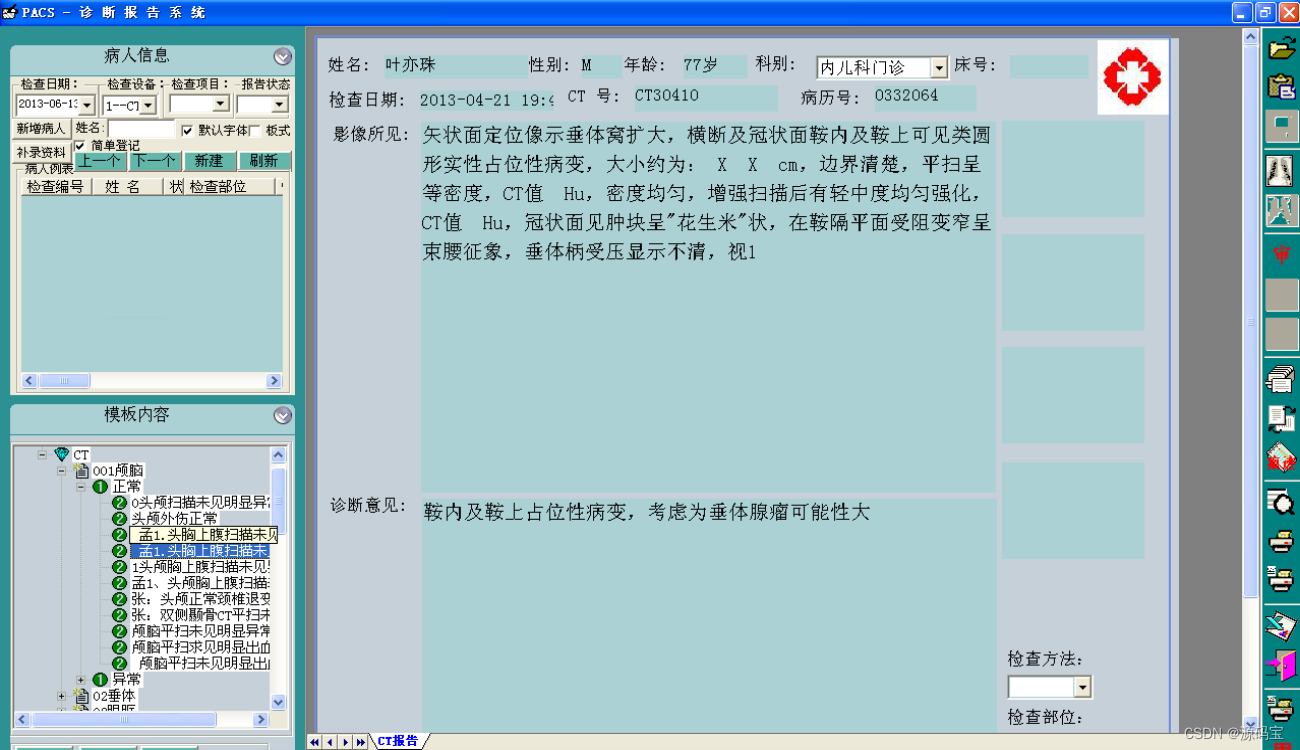

(4)分析诊断报告

提供专业丰富的诊断模板,并可以由医生添加、修改、删除,并可设置使用权限,可设置成医生独用或公用;

支持自定义报告样式,支持图文混排;

报告支持多级医生审核,支持典型病例管理;

报告所见即所得,支持报告打印自动缩放。